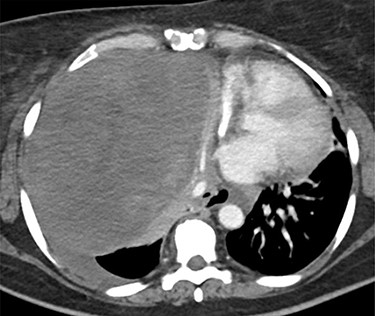

This is the case of a healthy 54-year-old female with a 3 month history of worsening dyspnea on exertion, nonproductive cough, general malaise and arthritic symptoms of her distal joints. Also, with an associated new onset, 6-month history of clubbing of her nails. She denied smoking history, weight loss, fever or chills. On examination she was found with clubbing of her nails (see Figs 1 and 2), and absent right thoracic breath sounds. Initial Chest X-ray (CXR) revealed a right side intrathoracic mass occupying the right thoracic cavity (see Fig. 3). She underwent a Chest computerized tomography (CT) scan with intravenous contrast revealing a large heterogenous mass 19 cm × 16 cm × 15 cm without gross calcifications (See Fig. 4). Then a CT-guided core needle biopsy was performed and was consistent with a benign SFT. In view of the mass size and worsening dyspnea, mass excision was performed by a single right side thoracotomy.

Chest CT scan. Large heterogenous mass in the right hemithorax, displacing the heart, great vessels and trachea, and esophagus to the left of midline. The origin may be hilar. No definite calcifications. Unrelated to vessels, and with associated left pleural effusion.